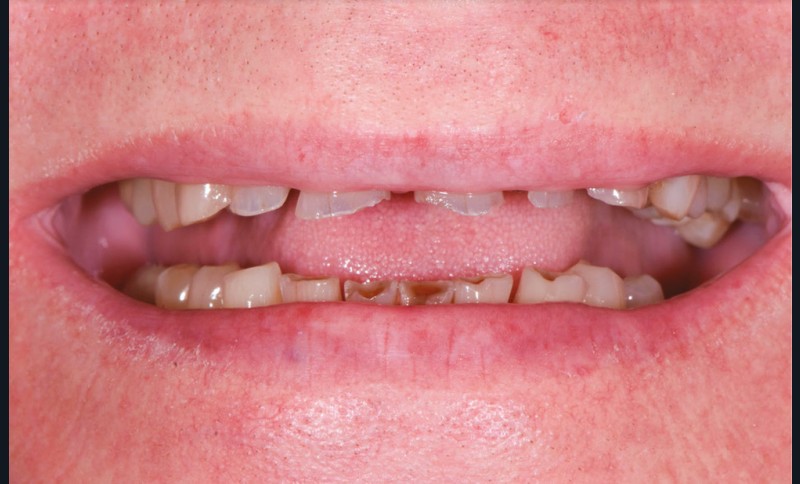

Un patient âgé de 69 ans se présente en consultation pour des problèmes d’ordre fonctionnel et un sourire dégradé. Selon l’adage de Peter Dawson, « l’esthétique et la fonction vont main dans la main », ce cas clinique illustre une situation instable et dysfonctionnelle qui ne sera résolue qu’avec une réhabilitation de la fonction et de l’esthétique (fig. 1 et 2).